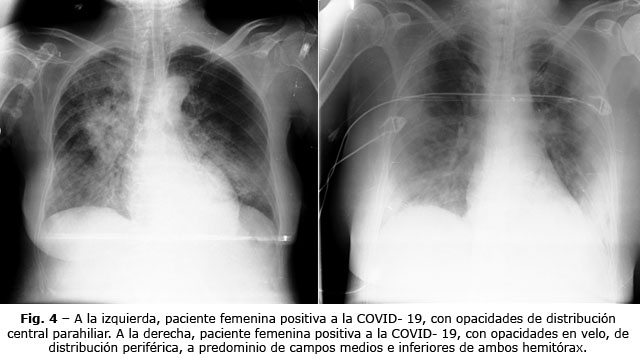

En la figura 3, se muestran los patrones de las radiografías; el 48,9 % presentó opacidad en velo de distribución periférica. Las lesiones caracterizadas por opacidad en velo con áreas de consolidación segmentaria y las opacidades de distribución central parahiliar, estuvieron presentes en el 19,2 %. Obsérvese en la figura 4, las radiografías que indican las imágenes características de pacientes con la COVID-19.